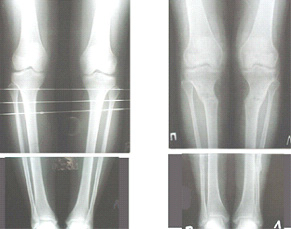

Вот ещё картинки, которые отправлял в Ортопод. Коррекция кривизны и удлинение на 3 см.

|